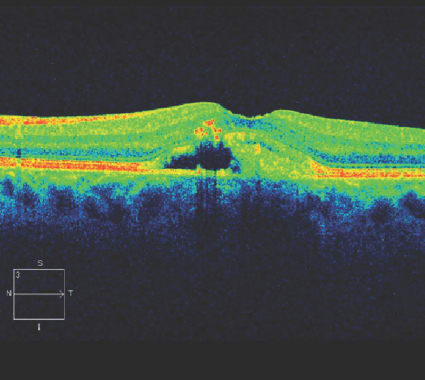

Clinically, adult vitelliform dystrophy looks like wet AMD, with an elevation of the retina that can be mistaken for subretinal fluid. I frequently see patients who are seeking a second opinion because they have been receiving anti-VEGF injections for AMD but have not been responding. Some of these patients actually have adult vitelliform dystrophy, which is not helped by anti-VEGF injections. On OCT, adult vitelliform dystrophy has a characteristic appearance (Figure 2). Once you recognize it, it is easy to see and understand. Similarly, if you do not see choroidal neovascularization on OCT, the patient may not have AMD.

Figure 2. This patient was treated with monthly anti-VEGF injections for almost a year before seeking a second opinion. Although the features, especially in an older patient, can be similar, the vitelliform lesion has a characteristic appearance on SD-OCT that differentiates it from choroidal neovascularization.